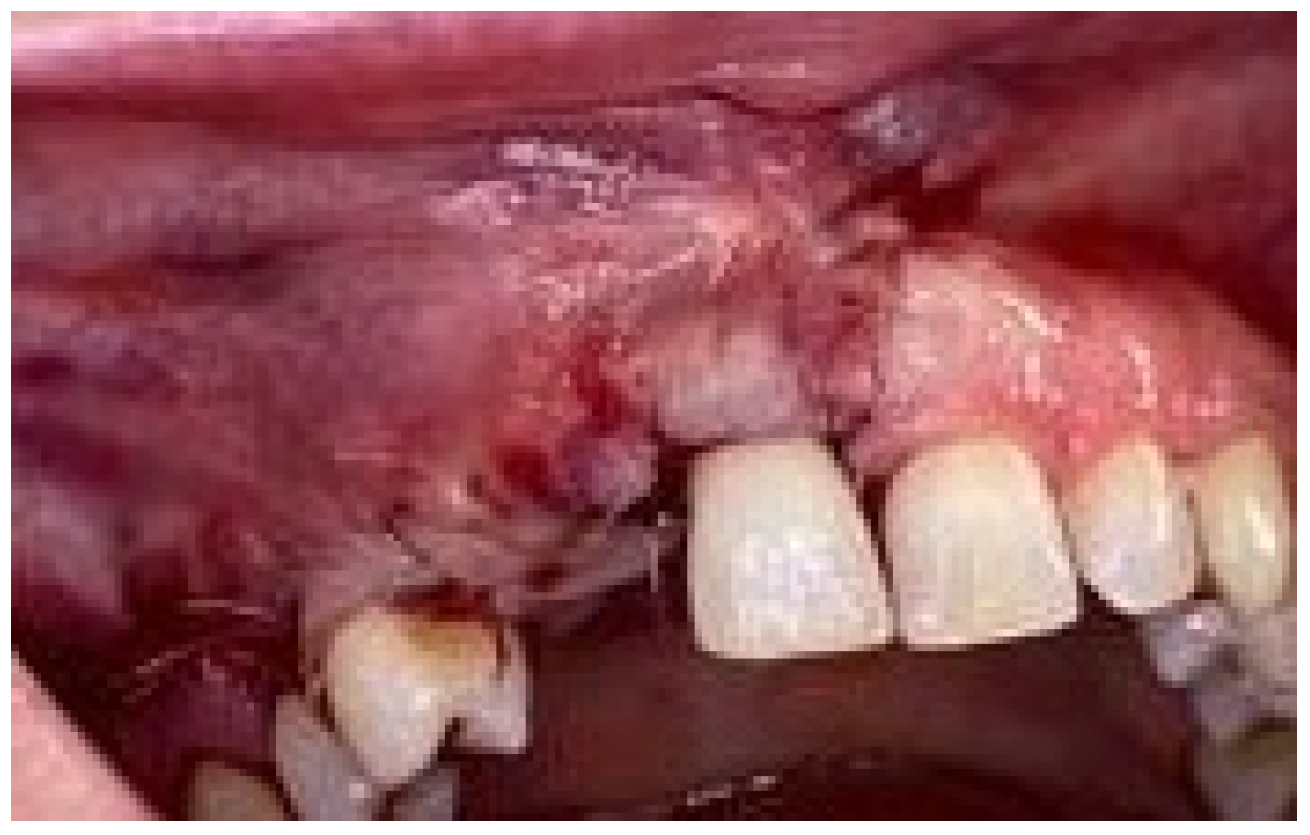

2. Case Presentation